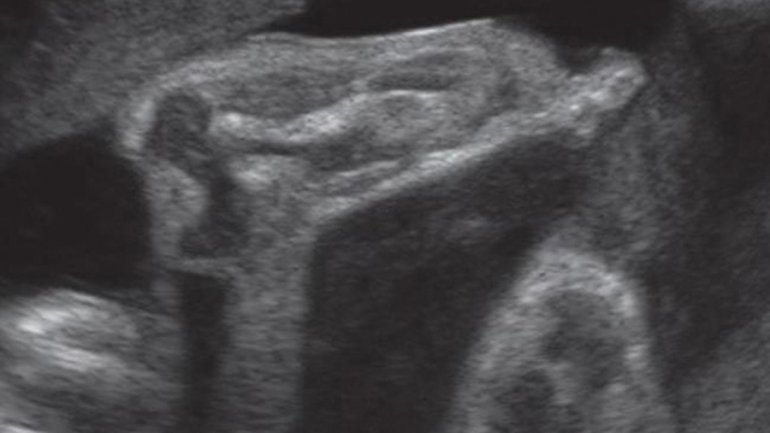

Ultraschall 18. SSW

Auf dem Ultraschallbild erkennt man mit etwas Übung beide Hände und einen Fuß: Von rechts unten kommt der Fuß ins Bild, die Zehen zeigen nach links oben. Der Fuß liegt über den beiden Händen, die überkreuzt sind. Eine Hand kommt dabei von oben rechts ins Bild, die Finger beider Hände fächern sich nach links auf.